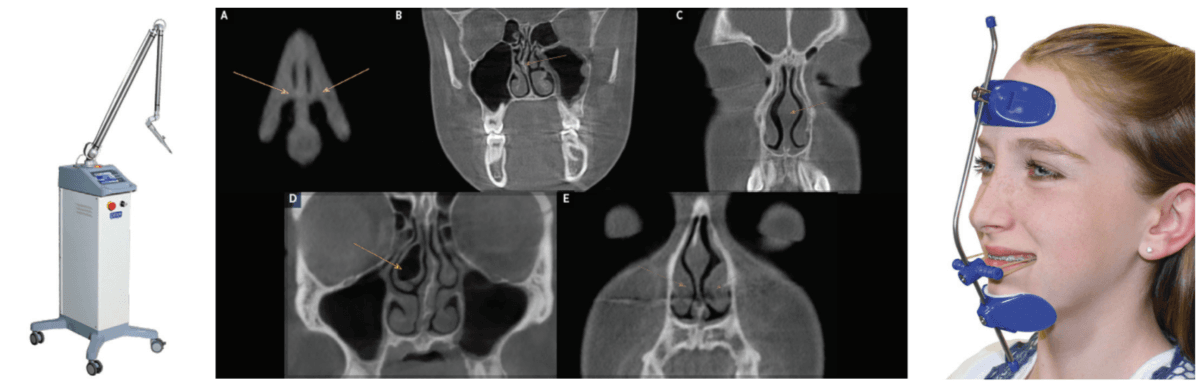

The only study to follow children post-T&A surgery over a 3-year period (with systematic evaluation using PSG at 6, 12, 24, and 36 months) showed that there was a 75% relapse of SD after 6 months.33 A pilot study utilizing CO2 laser (Deka/Bio Research Inc., Figure 3) to shrink palatal and base of tongue tissue for incomplete responders of oral appliance therapy (OAT) for OSA is currently underway at the University of Alberta School of Dentistry, Edmonton, Canada, by the principal investigator Enoch T. Ng, DDS, PhD (Figure 3). He has published a case report on the effectiveness of photobiomodulation for pediatric hypertrophic tonsils.34 These devices may someday be FDA-cleared to shrink tonsils. The morbidity and mortality of T&A surgery could be replaced with dentists performing a simple and painless technique.

A second line treatment to treat POSA is positive airway pressure therapy (PAP), most often utilizing continuous positive airway pressure (CPAP). Midface deficiency and POSA are highly comorbid. This is demonstrated by the incidence of children with Down syndrome who have POSA after T&A surgery at 65%-73%.35-38 CPAP use on children with POSA has been shown to prevent normal maxillary development and increase midface deficiency, thus making the patient more dependent on PAP.39 Maxillary development has been demonstrated to improve POSA and nasal function by increasing volume.40,41 It has been shown that maxillary expansion can shrink T&A and increase the internal nasal valve (which is the first point of entry of air into the nose).42,43 Nasal valve compromise (narrowing of the internal nasal valve) has been found to result in a 7-times greater chance of TM joint capsulitis and facial and cervical myositis, via mouth breathing, when compared to other nasal obstructions (Figure 4).44